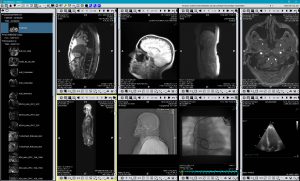

TM-PACS

Permette di comprimere, proteggere, salvare e visualizzare immagini radiologiche con strumenti di visualizzazione all'avanguardia (zoom, lente di ingrandimento, annotazioni, misurazione delle distanze, monitoraggio delle misurazioni ecc.). L'utente può visualizzare immagini angiografiche coronariche, immagini PET di medicina nucleare e le più tradizionali immagini (MRI, TC, ecografiche ecc.). L'applicazione di etichette consente di formare gruppi di esami e di accedervi tramite un semplice clic. Un sistema di ricerca personalizzato recupera rapidamente la cartella del paziente o l'esame desiderato. La soluzione è ottimizzata per la visualizzazione multischermo con integrazione dei software RIS e PACS, installati presso le stesse stazioni di diagnosi.